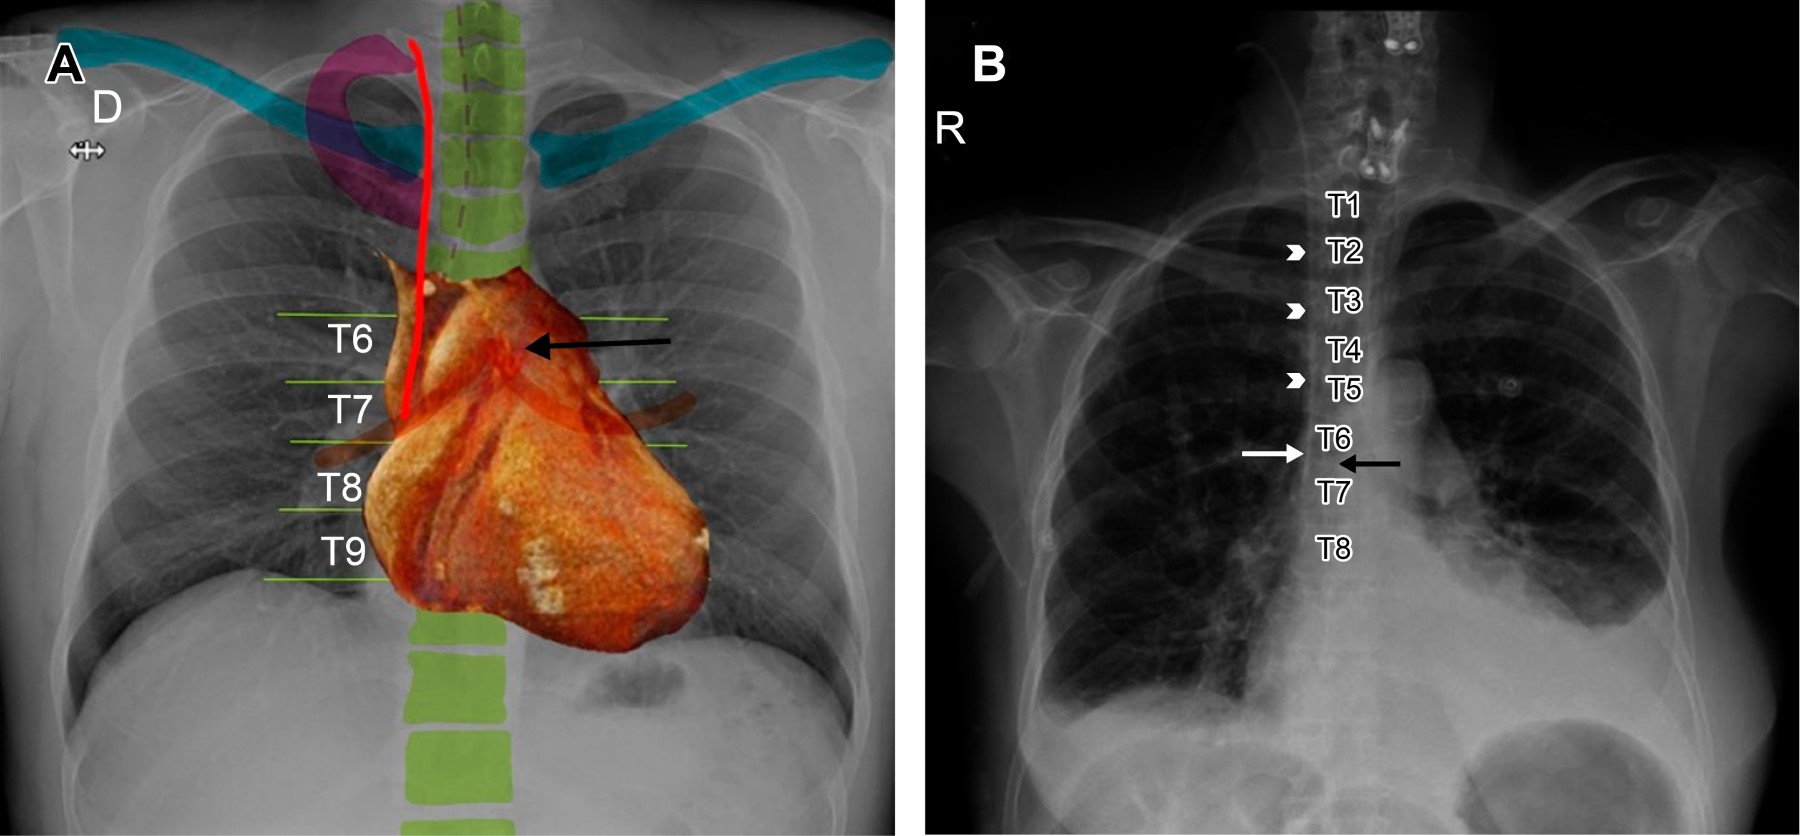

La situación ideal del tubo endotraqueal está dada por la distancia entre el extremo distal y la carina; en la literatura se considera que la posición correcta es de entre 3 y 7 cm superior a ésta, con el cuello en posición neutra, ya que con la extensión o la flexión del mismo es posible modificar la altura de la punta del tubo de hasta 2 cm de diferencia.6-8 También se describe la relación con las cuerdas vocales, considerando una distancia óptima de 3-4 cm inferior a esta estructura para evitar lesión o extubación espontánea.1,3,9 La tomografía y resonancia magnética son las modalidades de imagen ideales para su evaluación.

Cuando no se logra identificar la carina, debemos recordar que normalmente se encuentra entre los cuerpos vertebrales T5 y T7 en 95% de los pacientes.1 Existen otros marcadores anatómicos para determinar si el extremo distal del tubo tiene una posición óptima, y podemos usar de referencia los cuerpos vertebrales T2-T4,6,8 los bordes mediales de las clavículas o la porción caudal del arco aórtico (Figura 1A y B).10

El trayecto de VCS nos ofrece otras referencias anatómicas, ya que sigue un curso perpendicular y ulterior al segundo y tercer espacio intercostal (línea paratraqueal derecha), alcanzando la unión cavoatrial (Figura 3) antes de ingresar al pericardio (borde superior del tercer cartílago costal derecho), y posteriormente ingresar al saco pericárdico.9 En la radiografía, Baskin KM y colaboradores proponen situar la unión cavoatrial dos cuerpos vertebrales por debajo de la carina. Diversos autores recomiendan que todas las puntas de catéter deben situarse por encima de la carina.9,20